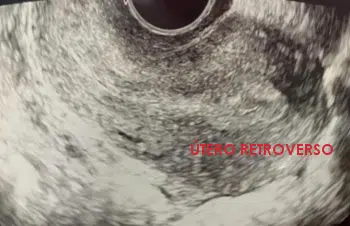

Dentro del estudio que realizamos a nuestras pacientes cuando inician un tratamiento de reproducción asistida se encuentra la valoración ecográfica de los órganos reproductivos femeninos:

Cuando visualizamos el útero por ecografía, valoramos los parámetros descritos.